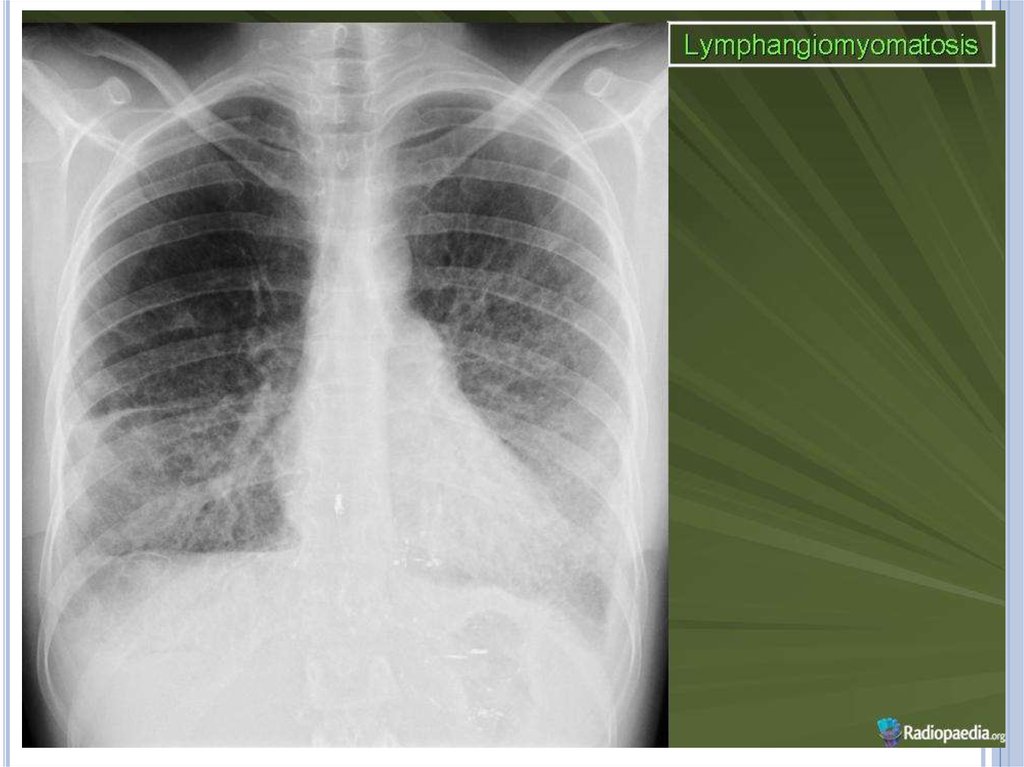

Инструментальные методы исследования

Рентгенологическое исследование легких - признаками

ЛАМ легких на обычных рентгенограммах грудной клетки

являются:

усиление легочного рисунка сетчатого характера;

увеличение объема легких.

Наиболее характерный морфологический признак ЛАМ кистозная трансформация легких, которая обычно выявляется

на компьютерных томограммах. Кисты бывают двух типов:

мелкие множественные типа «сотового легкого» и

крупные кисты, присущие буллезной эмфиземе.

Толщина стенки кисты не превышает 2 мм, причем стенка

кисты выявляется не всегда и не на всем протяжении.

Окружающая легочная ткань часто не изменена. Однако

сочетание фиброзных и кистозных изменений не

противоречит диагнозу ЛАМ. Таким образом,

рентгенологическая картина ЛАМ не патогномонична.

Ведущим рентгенологическим признаком этого заболевания

является образование множественных воздушных

11.

Для очаговой формы характерны очаги затемнения от 0,5 до

1,5 см в диаметре с четкими границами.

При развитии пневмоторакса определяется спавшееся

поджатое воздухом легкое, при развитии хилоторакса интенсивная гомогенная тень (за счет выпота) с

косовосходящей верхней границей.